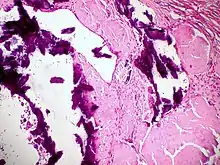

Histopathology of dystrophic microcalcifications in ductal carcinoma in situ of the breast, H&E stain. In contrast to an artifact of crowded cells, the calcification characteristically extends outside the focal plane, as the background DCIS is blurred in this focus.

Dystrophic calcification (DC) is the calcification occurring in degenerated or necrotic tissue, as in hyalinized scars, degenerated foci in leiomyomas, and caseous nodules. This occurs as a reaction to tissue damage,[1] including as a consequence of medical device implantation. Dystrophic calcification can occur even if the amount of calcium in the blood is not elevated, in contrast to metastatic calcification, which is a consequence of a systemic mineral imbalance, including hypercalcemia and/or hyperphosphatemia, that leads to calcium deposition in healthy tissues.[2] In dystrophic calcification, basophilic calcium salt deposits aggregate, first in the mitochondria, then progressively throughout the cell. These calcifications are an indication of previous microscopic cell injury, occurring in areas of cell necrosis when activated phosphatases bind calcium ions to phospholipids in the membrane.